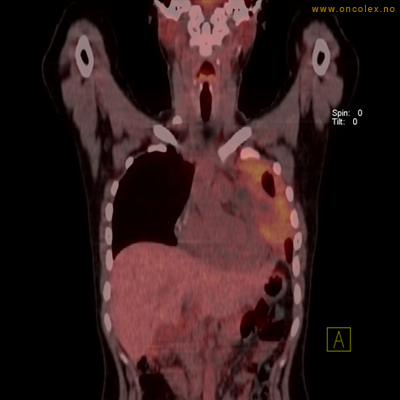

Eksempler på funn

Vev som tar opp mer radioaktivt stoff, synes som hvite områder som lyser opp mer i forhold til annet vev som tar opp mindre sukker.